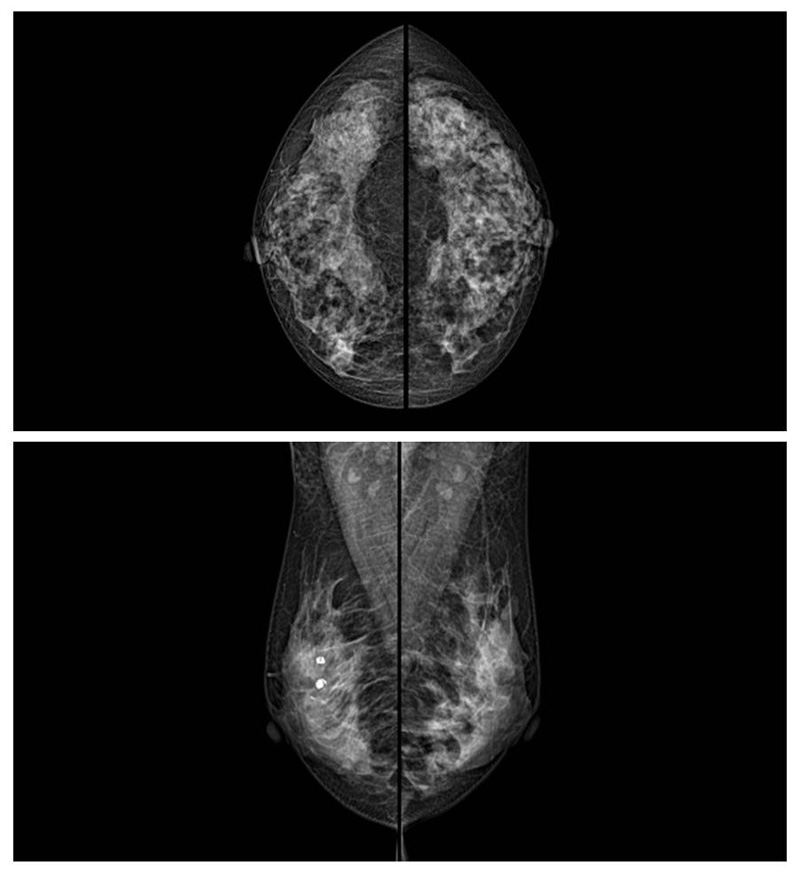

乳腺癌的發(fā)生率越來越高,已經(jīng)是我們國家的癌癥之一已成為女性健康“頭號殺手”。乳腺DR可提高乳腺癌早期檢出率并精準(zhǔn)定位。發(fā)現(xiàn)和診斷早期乳腺癌最有效的方法之一,明顯利大于弊女性都要重視乳腺的檢查。輻射很小最簡便、最可靠、無創(chuàng)性檢查手段,做一次乳腺DR的劑量相當(dāng)于7周的正常生活。尤其是對于40歲以上的女性尤為重要,那么乳腺DR是怎么進(jìn)行檢查的呢?我們來了解一下,為廣大朋友在檢查前有點(diǎn)心理準(zhǔn)備。檢查時候是避開經(jīng)期的前后,月經(jīng)來后的7天左右比較合適。需要脫衣服檢查,根據(jù)拍片的擺位要求,有頭尾位置,內(nèi)外斜位,還有側(cè)位。定點(diǎn)放大壓迫方法可以更細(xì)微清晰的檢查出病灶。